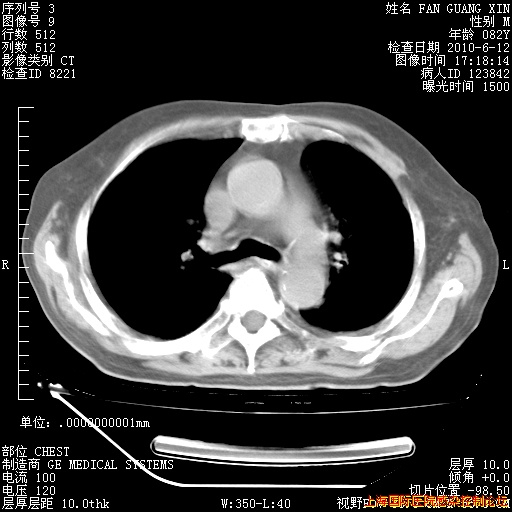

补发6月12日肺部CT肺窗

6月12日肺窗

6月12日纵膈窗